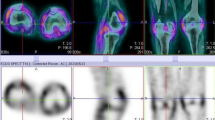

Overall, the study was well tolerated, with none of the patients presenting with any adverse events. All 22 participants had abnormal increased uptake of the radiopharmaceutical in their affected joints, with SPECT/CT imaging localizing uptake specifically to the synovial space as seen in Fig. 2. Of the 22 flow studies, 10 (45%) participants had normal flow to their most symptomatic joints, with 12 (55%) having increased flow to their most symptomatic joints. Increased flow studies were associated with either grade 3 or 2 disease on the delayed static images as shown in Fig. 3. Good quality images were obtained 2 h post 99mTc-ECDG administration, with an optimal target to background ratio. The majority of the participants had the greatest uptake of radiotracer in their most clinically active joints (n = 15, 68%). The mean DAS-28 score for all the participants was 41, with a range of 17–67. Majority of the participants had high DAS-28 scores indicating severe disease as seen in Table 1 showing the characteristics of the study population. All participants with clinically severe disease had an overall grade 3 or 2 uptake of 99mTc-ECDG on their scans, with 55% being grade 3 uptake. Twelve participants had evidence of disease in other joints outside the hands, wrists, and knees. These joints included the shoulders (n = 9), elbows (n = 4), and ankles (n = 2). Two participants presented with unilateral knee disease, as seen in Fig. 4. No incidental finding of extra articular disease was noted in any of the 22 participants.

Three phase 99mTc glucosamine scan of a 58-year-old female with rheumatoid arthritis that developed a flair after discontinuing her medications. The flow images (A) show increased blood flow to the region of the wrists and small bones of the hands. The blood pool and delayed static images (B and C, respectively) show increased blood pool and delayed activity to the wrists and small joints of the hands, respectively